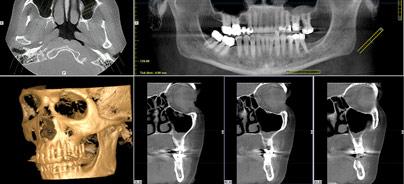

Moderne Diagnostik im Test – Erfahrungen mit Pan eXam Plus, KaVo

Jahr 2012, Ausgabe 04, Seite 36 Autoren: Priv.-Doz. Dr. Margrit-Ann Geibel

Dosisaspekte und rechtfertigende Indikationen in der 3-D-Radiologie

Jahr 2012, Ausgabe 01, Seite 6 Autoren: Priv.-Doz. Dr. Margrit-Ann Geibel

DVT-Kompendium von Dr. Margrit-Ann Geibel

Jahr 2011, Ausgabe 04, Seite 35 Autoren: Univ.-Prof. Dr. Gabriele Kaeppler, Ludwig-Maximilians-Universität München